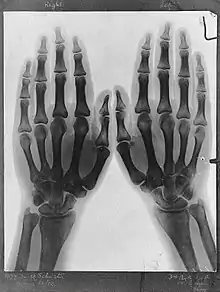

![]() X-ray of Norah Schuster's hands taken by her father.[1] | |

Norah Schuster was born on 14 July 1892, the daughter of the German-born British physicist Arthur Schuster who was the first to report the findings of Wilhelm Röntgen about X-rays in the United Kingdom.[3] Later in life, Norah described her father's initial uses of bedside X-rays taken in Manchester in 1896.[4] He gave public lectures on the new technique which Norah and her brother attended, X-rays of their hands and feet being used to illustrate the proceedings for which a ten minute exposure was required due to the weakness of the rays.[5]

- ↑ Two hands, viewed through x-ray. Photoprint from radiograph after Sir Arthur Schuster, 1896. Wellcome Library. Retrieved 16 February 2018.